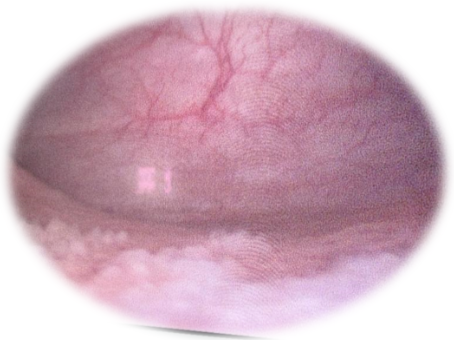

检查发现,患者膀胱内在三角区的粘膜有白色斑片状隆起改变或成片细小滤泡样突起改变,取这些异常组织,送病理检查确诊为腺性膀胱炎。

腺性膀胱炎主要与泌尿系慢性感染、泌尿系结石、异物刺激、精神因素、变态反应、盆底肌肉松弛等有关。当反复出现尿频、尿急、尿痛、血尿、下腹或会阴区胀痛不适、排尿困难等症状时,就怀疑可能为腺性膀胱炎,建议要到医院进一步就诊确认。否则严重时可能会导致肾、输尿管积水等,部分患者的症状迁延反复,甚至可严重影响患者的生活质量。目前,对于腺性膀胱炎,主要的诊断依据是膀胱镜检查及活检(如下图)。